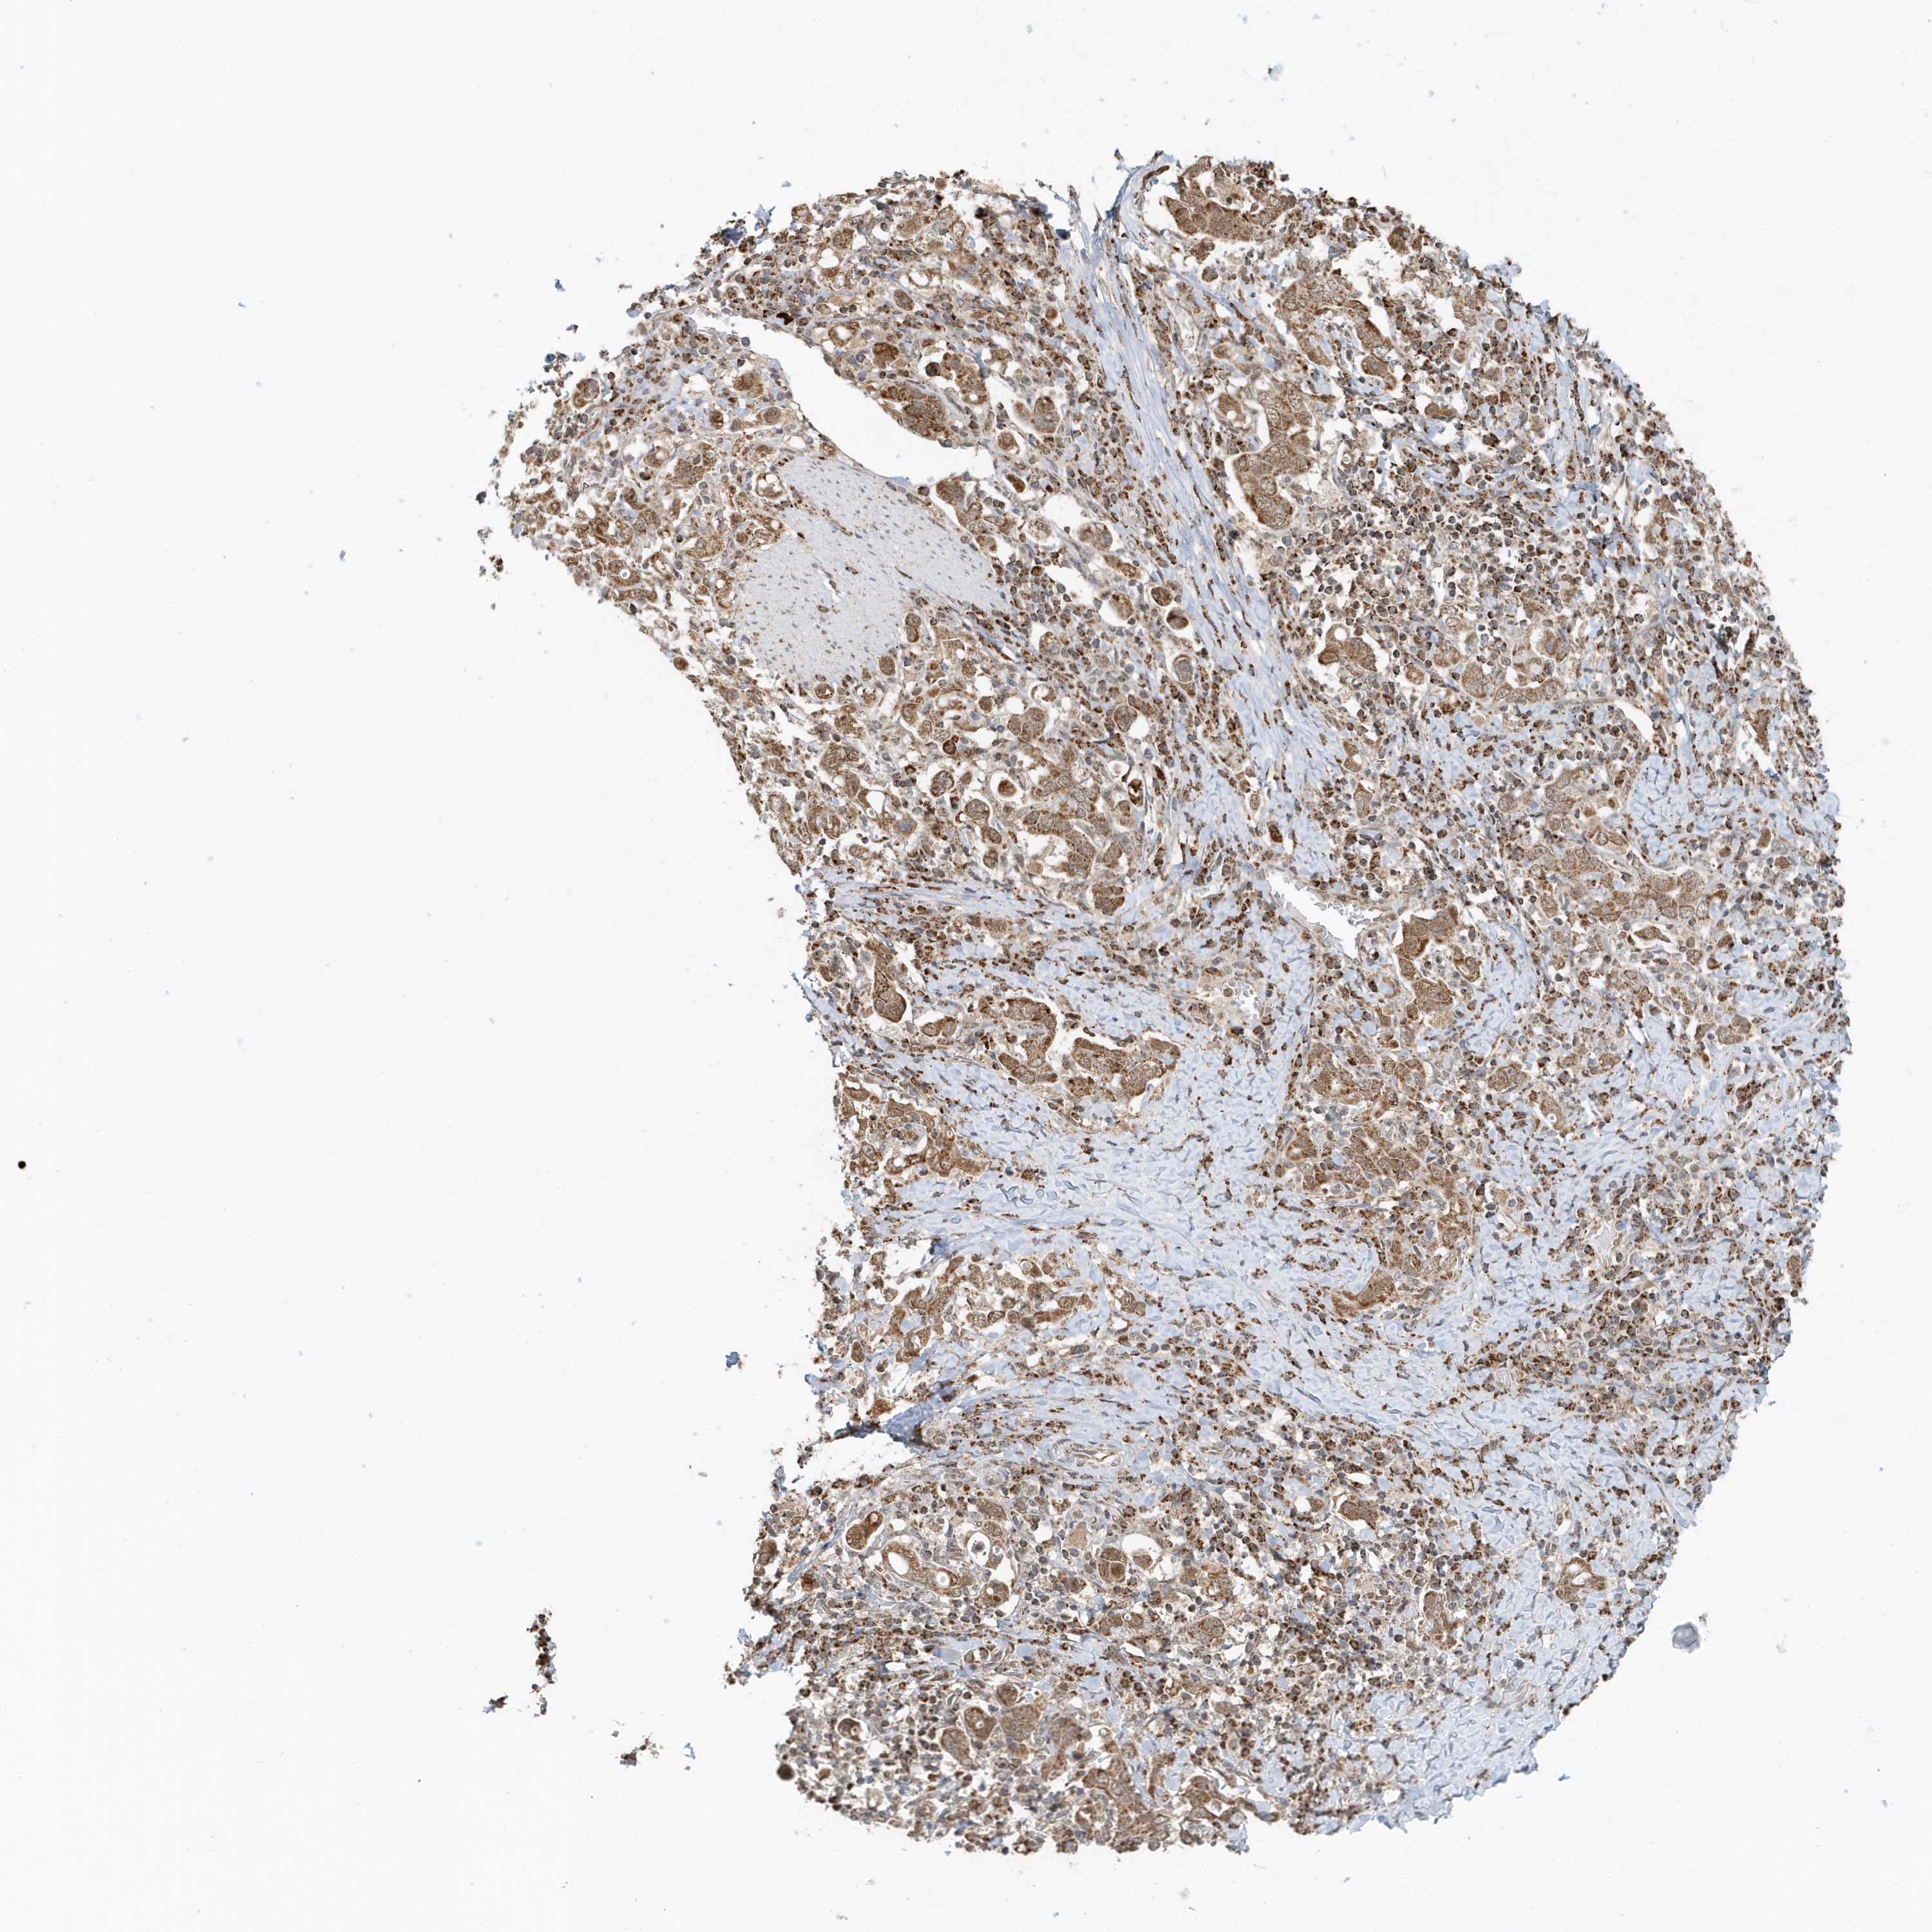

STOMACH CANCER - Protein expressioni

A mouse-over function shows sample information and annotation data. Click on an image to view it in a full screen mode. Samples can be filtered based on level of antibody staining by selecting one or several of the following categories: high, medium, low and not detected. The assay and annotation is described here.

Note that samples used for immunohistochemistry by the Human Protein Atlas do not correspond to samples in the TCGA dataset.

Antibody stainingi

Antibody staining in the annotated cell types in the current human tissue is reported as not detected, low, medium, or high, based on conventional immunohistochemistry profiling in selected tissues. This score is based on the combination of the staining intensity and fraction of stained cells.

Each image is clickable and will lead to virtual microscopy that enables deeper exploration of all samples and also displays staining intensity scores, fraction scores and subcellular localization as well as patient and tissue information for each sample.

Antibody HPA036921

Antibody HPA036922

Staining

High

Medium

Low

Not detected

Intensity

Strong

Moderate

Weak

Negative

Quantity

>75%

75%-25%

<25%

None

Location

Nuclear

Cytoplasmic/membranous

Cytoplasmic/membranous,nuclear

Adenocarcinoma, NOS